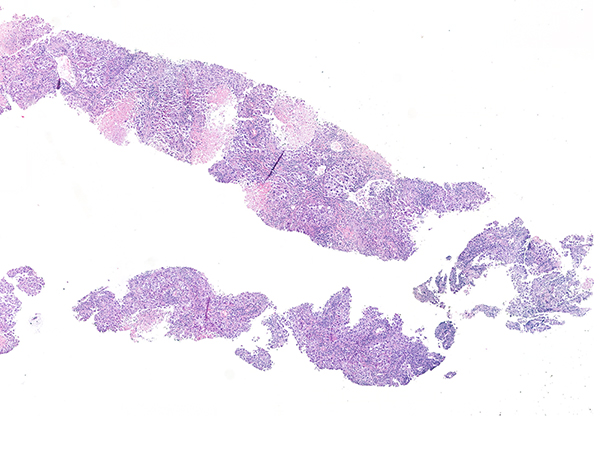

Clinical History: An 87-year-old male never smoker with multiple resected meningiomas presented with dyspnea. His CT shows multiple bilateral pulmonary nodules, with a dominant mass measuring 36 mm in the right upper lobe and mediastinal lymphadenopathies. No other history of cancer was known. A percutaneous lung biopsy was performed. Histological sections are shown in figures 1 and 2. Figure 3 corresponds to TTF1 (8G7G3/1) and figure 4 to p40.

In lung diagnostic samples, the amount of tissue is limited, and it needs to be used for accurate histological classification and, in many cases for biomarker testing. Well differentiated tumors with clear squamous or glandular differentiation do not require immunohistochemistry and a limited immunopanel of TTF1/p40 is sufficient in most cases to classify poorly differentiated tumors. Using this simple panel, cases that are positive for TTF-1 alone can be classified as non-small cell lung carcinoma (NSCLC) favor adenocarcinoma and p40 positive cases can be classified as NSCLC favor squamous cell carcinoma. Tumors that are negative for both TTF-1 and p40 can be reported as NSCLC not otherwise specified in a small biopsy. However, in this scenario, it is critical to consider an expanded differential diagnosis that should include metastasis from elsewhere, melanoma, sarcoma, lymphoma and other undifferentiated neoplasms. This requires reviewing the medical record and expanding the immunopanel. A diffusely positive keratin for example is enough to confirm the epithelial nature of the neoplasm.

From all the diagnostic possibilities it is important to always keep in mind melanoma because metastatic melanoma can have multiple clinical presentations. This famous mimicker can have multiple appearances from spindled to epithelioid with carcinoma-like morphology. There are also cases in which melanoma can have a lepidic growth architecture and extend along intact alveolar spaces. Some clues should make us suspect it: big nucleoli, rhabdoid features or cells infiltrating the interstitium in otherwise conventional “lepidic” neoplasm. But these features may lack like in our case.